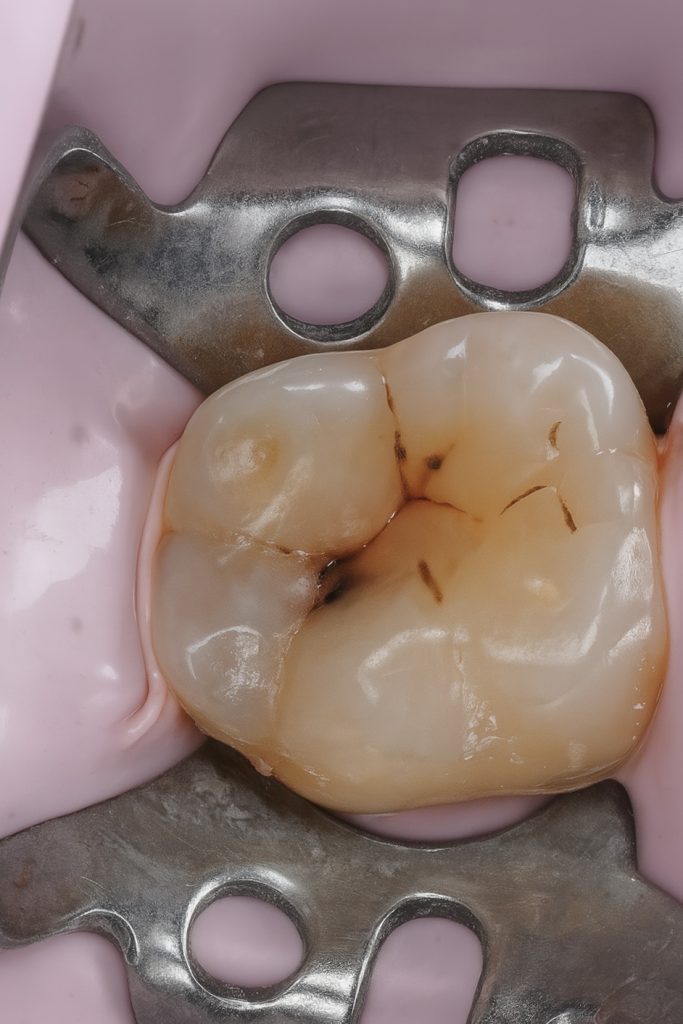

A mandibular first molar presented with localized occlusal caries (Fig 1). Under rubber-dam isolation, conservative cavity preparation was done, preserving pericervical dentin and enamel ridges. The cavity outline followed the carious extension only, minimizing healthy tissue removal.

- Fig 2: Cavity after caries removal and selective etching.